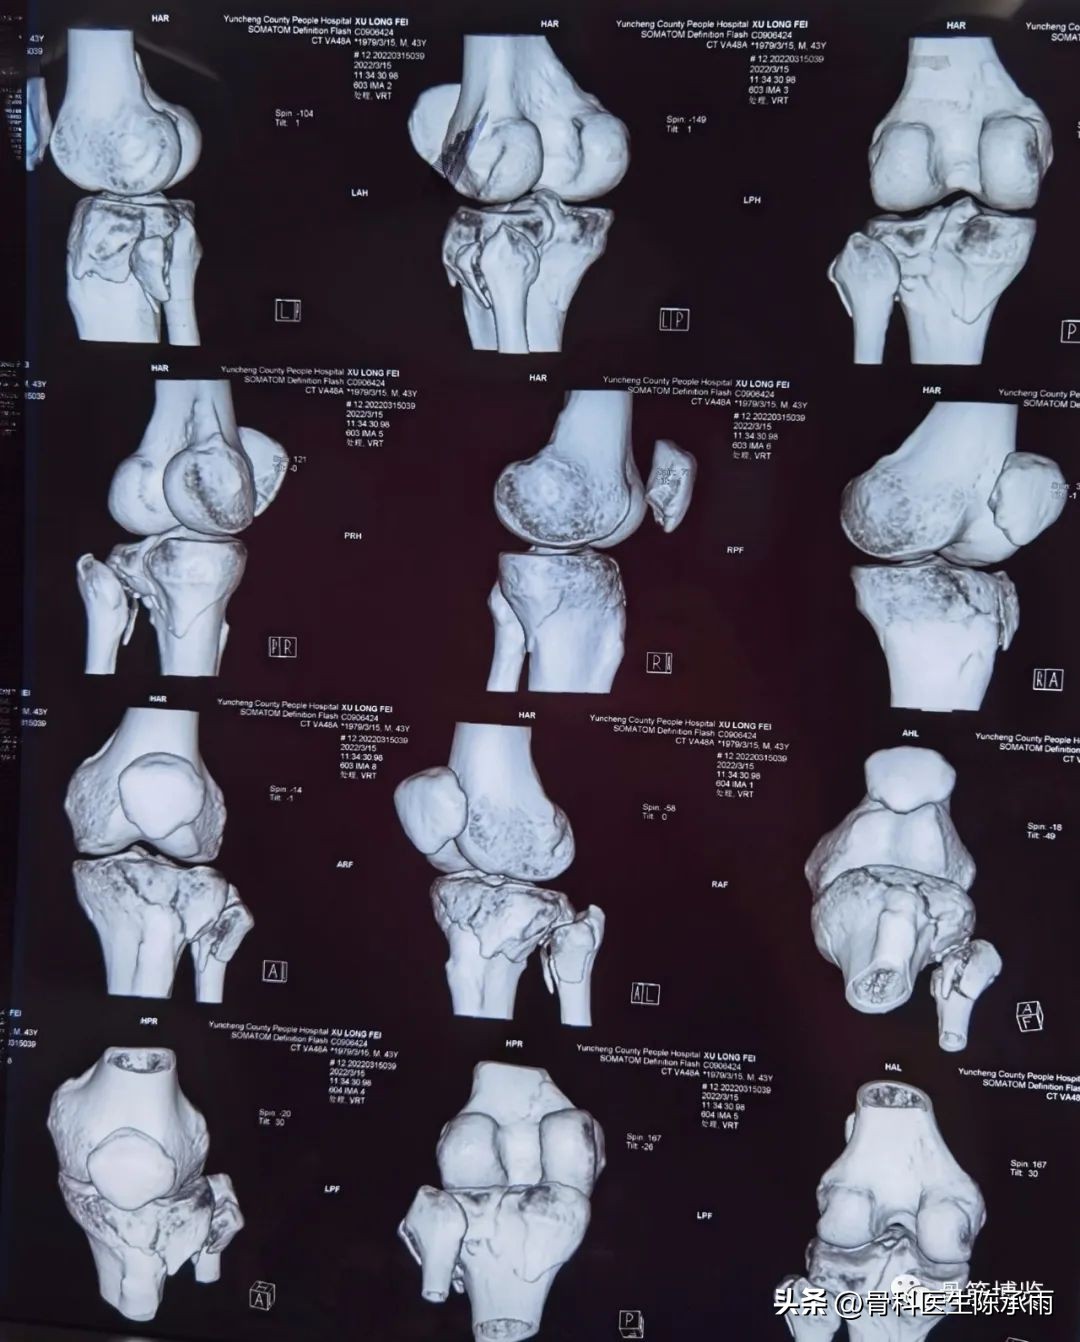

近段时间的胫骨平台骨折,没来得及详细整理

对AO 分型来讲,现在这是AO推出来更详细的,再分为ABC。随着分型的增加,从A到C骨折的损伤程度是越来越重,治疗也越来越困难,从1到2 ,123也是这个规律,骨折的分型就是给我们表明了骨折的一个损伤的程度,治疗办法和损伤的特点。我们对于骨折脱位的分型,常用Hohi-Moore分型,这个是弥补了,Schatzker和AO分型的一些缺陷。